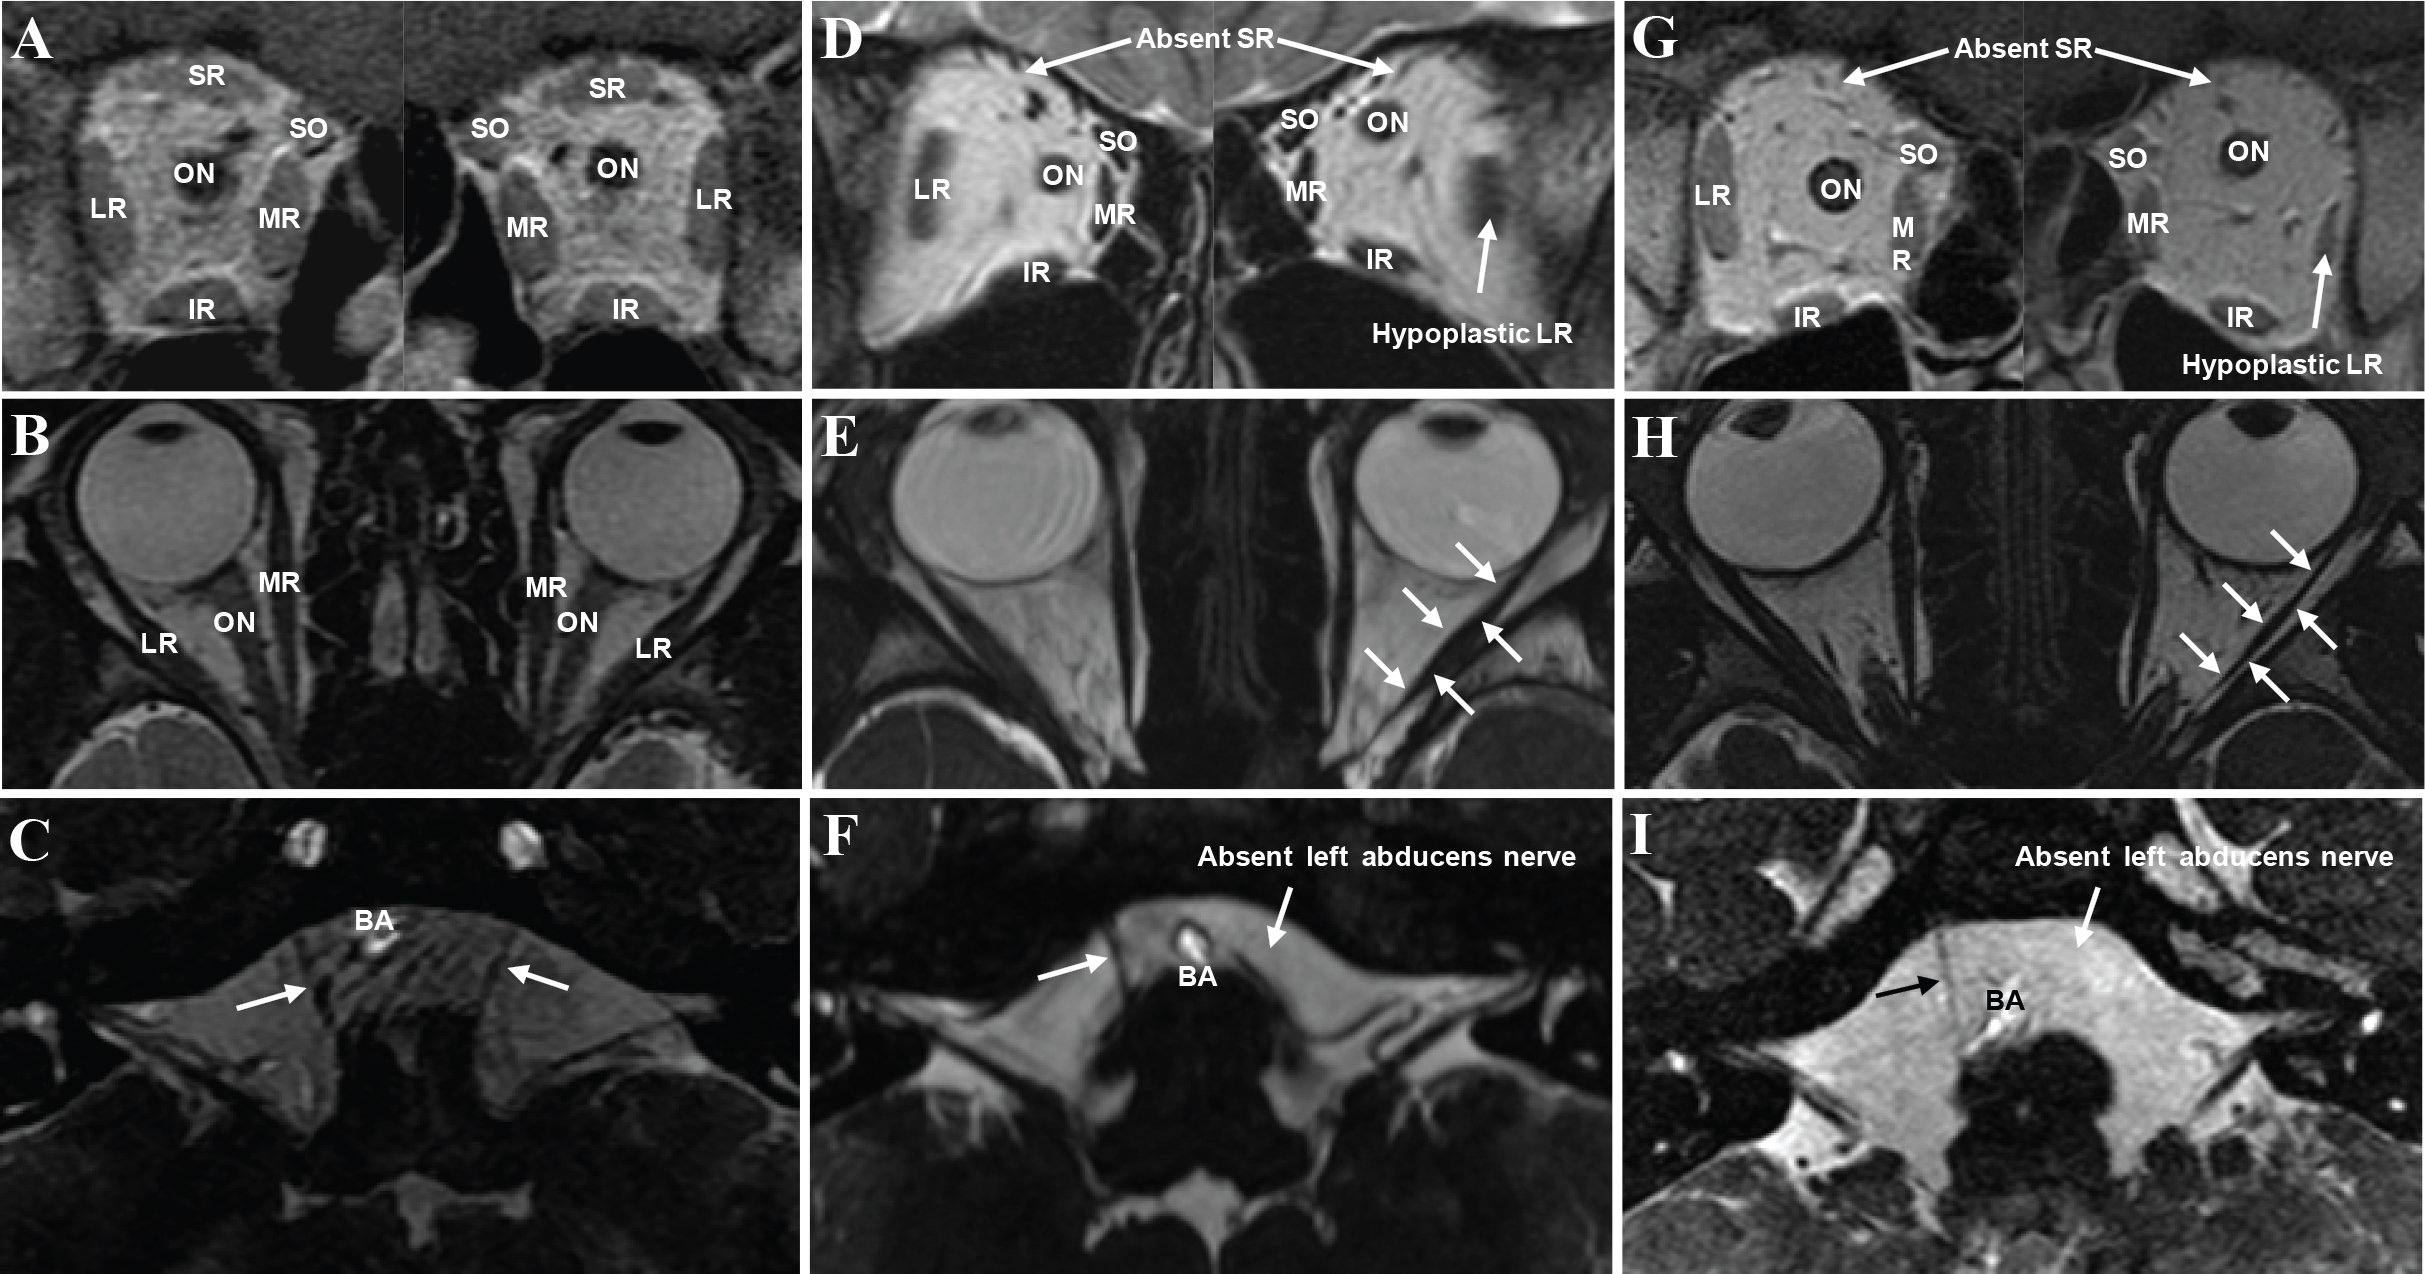

Figure 3. Imaging of the extraocular muscles and abducens nerves. A–C: Normal aspects of the extraocular muscles (EOMs) and bilateral abducens nerves are presented by coronal and axial magnetic

resonance imaging (MRI) in a control individual. D: Coronal MRI of the bilateral orbits of patient II:1 showed the absence of bilateral superior rectus (SR) muscles and hypoplasia

of the left lateral rectus (LR) muscle but a normal LR muscle of the right eye. E: The axial MRI of patient II:1 showed adduction of the left eye. The LR muscle (arrows) of the left eye was small and had

a string-like configuration, suggesting fibrosis. In contrast, the LR muscle of the right eye was of normal size with a spindle

shape. F: The axial MRI illustrates the absence of the left abducens nerve in patient II:1. G–I: Patient II:2 presented similarly to patient II:1 by showing absence of bilateral SR muscles and small left LR muscle in

the coronal MRI. The axial MRI of both orbits reveals the fibrosis of the left LR muscle (arrows) and adduction of left eye.

An absence of the left abducens nerve was also demonstrated by the axial MRI. Abbreviation: MR, medial rectus; IR, inferior

rectus; SO, superior oblique; ON, optic nerve; BA, basilar artery.